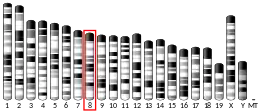

| |||||||||||||||||||||||||||||||||||||||||||||||||||

| |||||||||||||||||||||||||||||||||||||||||||||||||||

| |||||||||||||||||||||||||||||||||||||||||||||||||||

| |||||||||||||||||||||||||||||||||||||||||||||||||||

| |||||||||||||||||||||||||||||||||||||||||||||||||||

| |||||||||||||||||||||||||||||||||||||||||||||||||||

| |||||||||||||||||||||||||||||||||||||||||||||||||||